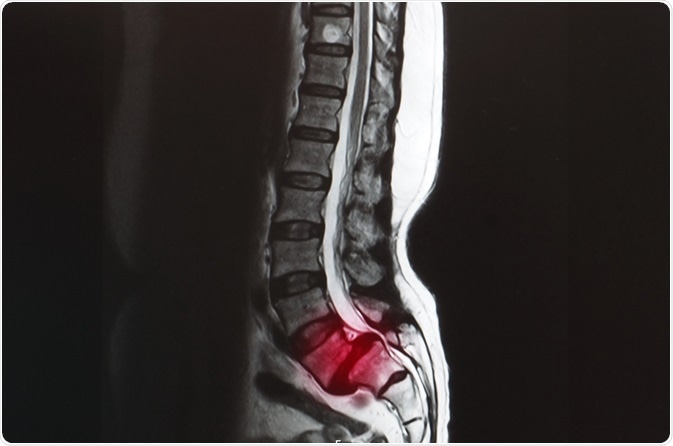

Spondylolisthesis. Image Credit: Yok_onepiece/Shutterstock.com